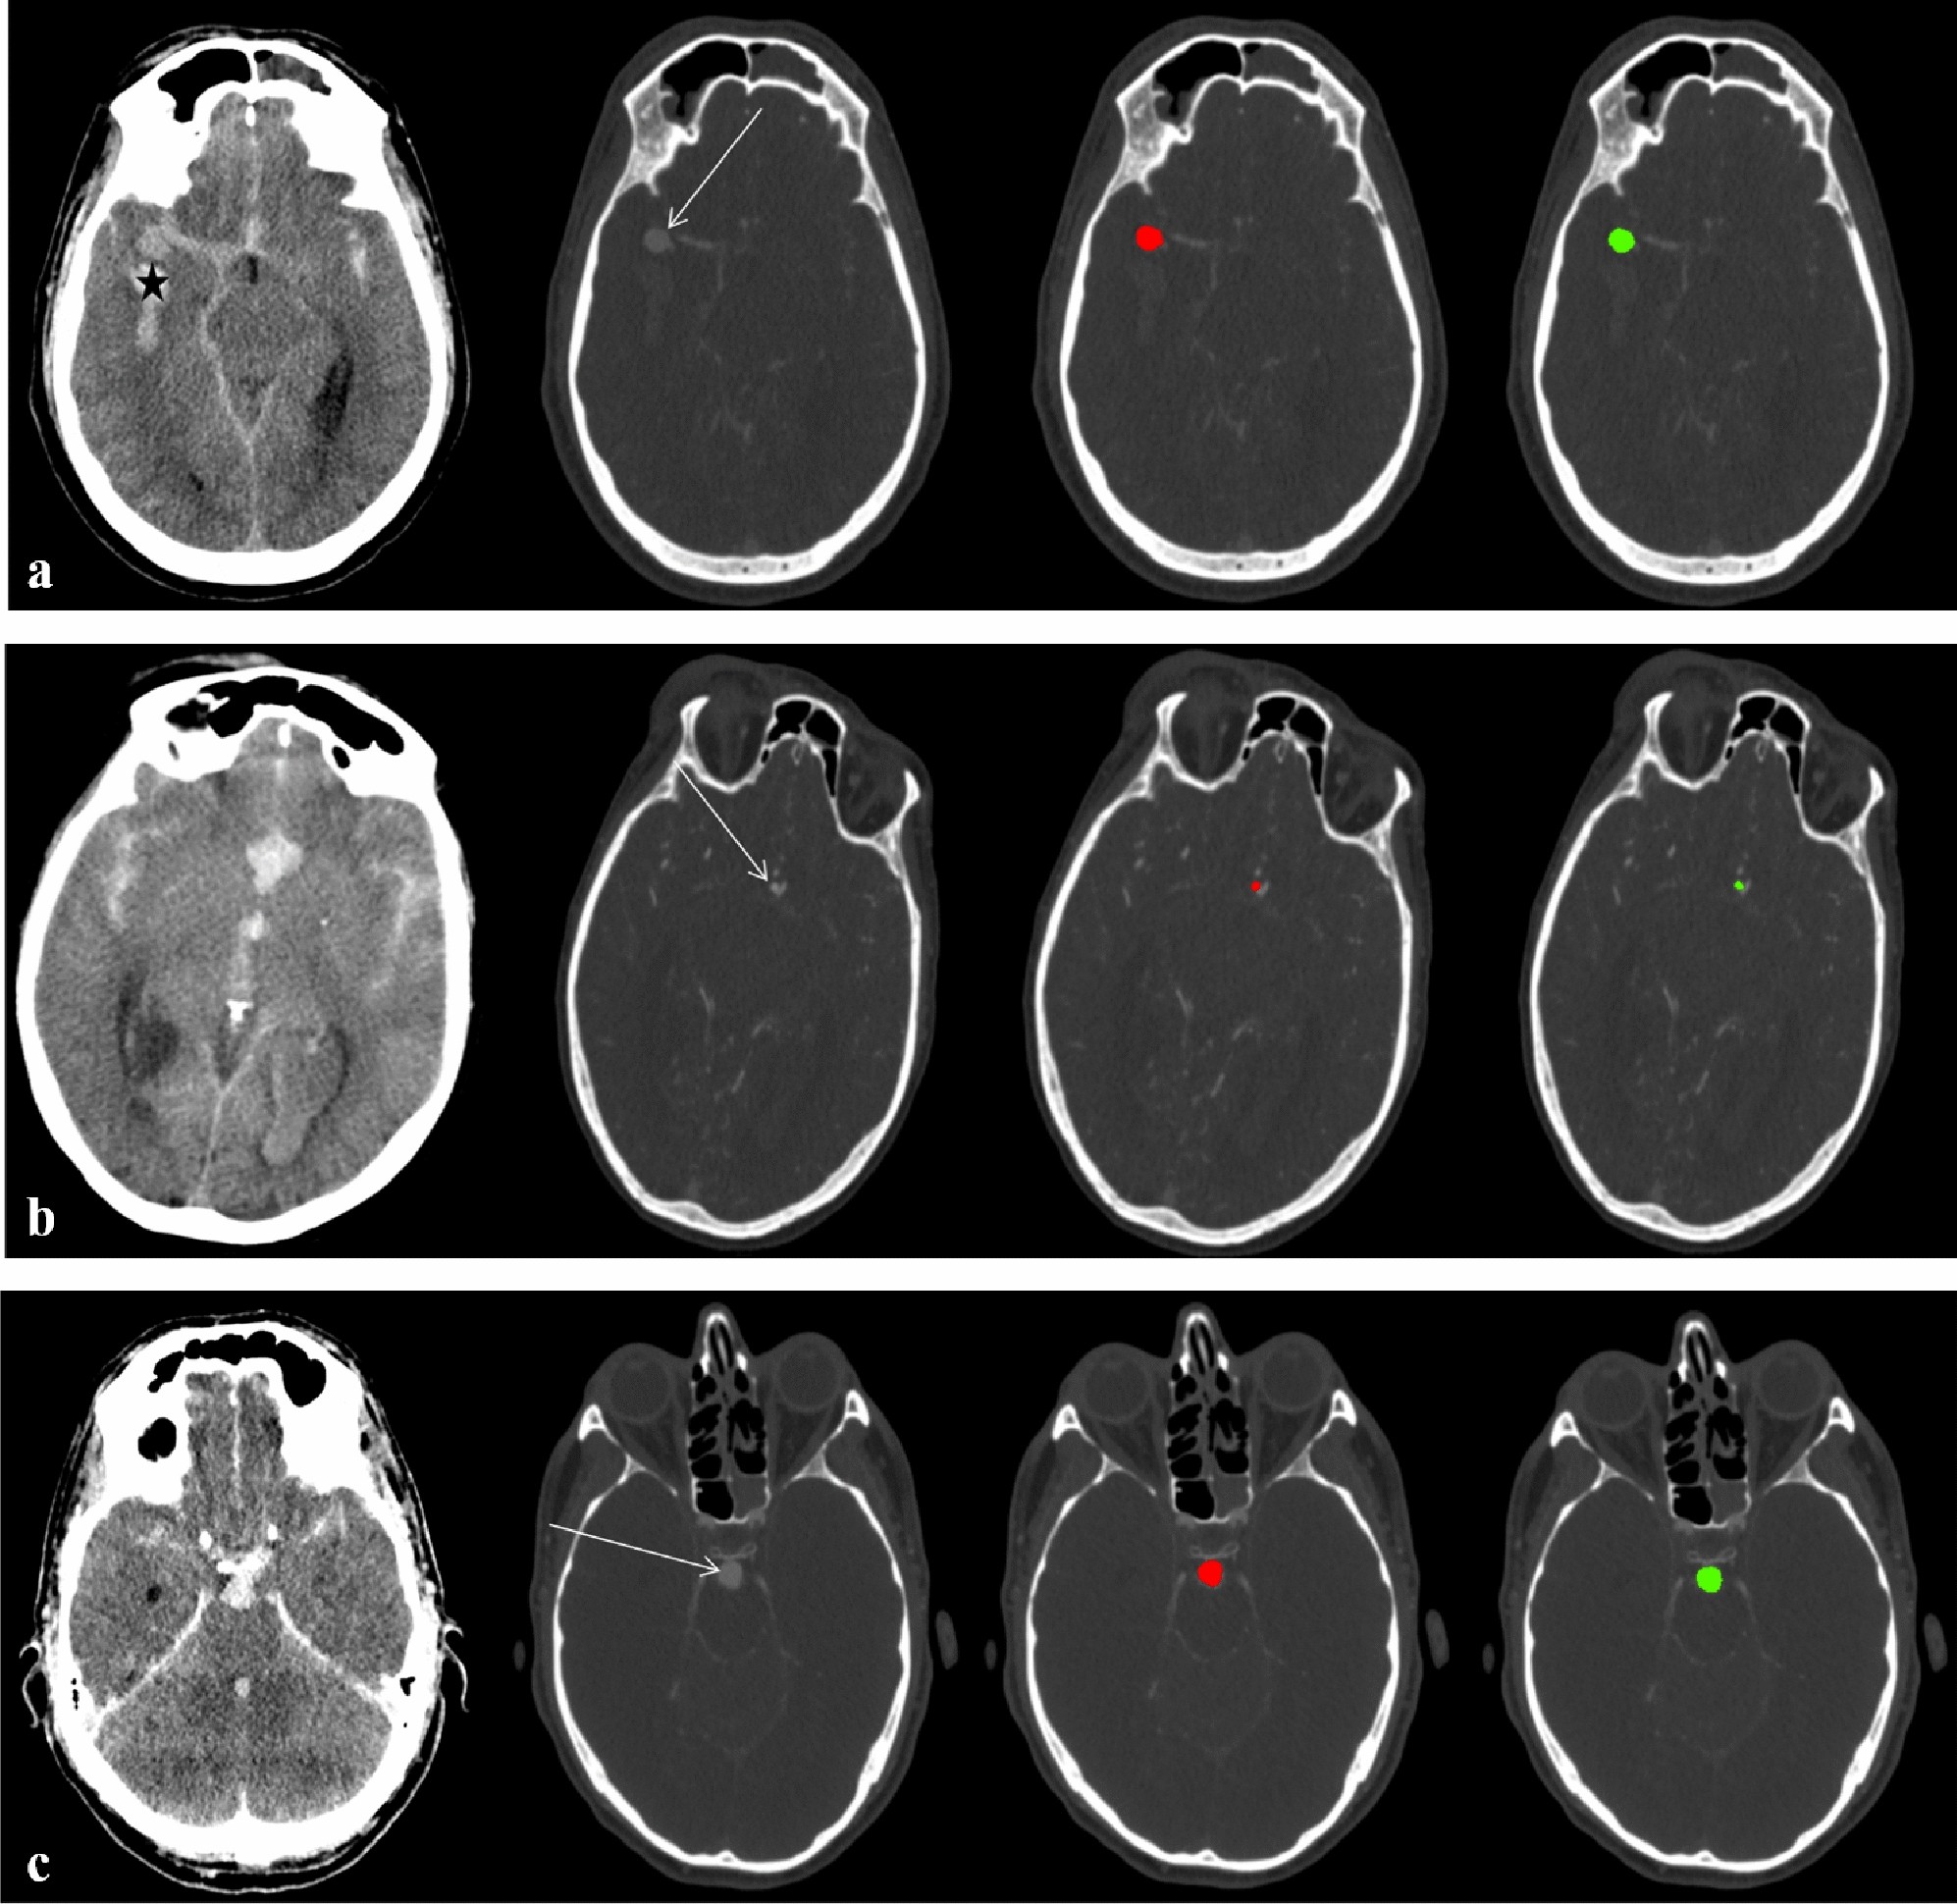

(a) Fifty-one-year-old male with Fisher 4 bleeding (* = intraventricular bleeding on axial unenhanced CT) and an aneurysm of the right middle cerebral artery (arrow) on axial CTA

source images. The DLM-Ens (green) detects and segments the aneurysm (volume based on manual segmentation: 424.7 mm3) with high overlap (DSC of 0.94) compared to manual segmentations (red). (b) Sixty-three-year-old female with aSAH on axial unenhanced CT and an anterior communicating artery aneurysm (arrow) on axial CTA source images. Albeit being of small size (volume based on manual segmentation: 25.5 mm3), the DLM-Ens (green) detects and segments (DSC of 0.72) the aneurysm with high overlap compared to manual segmentations (red). (c) Fifty-one-year-old male with aSAH on axial unenhanced CT and a large basilar tip aneurysm (arrow; volume based on manual segmentation 419.6 mm3) on axial CTA source images. Compared to manual segmentations (red), the DLM-Ens (green) provides accurate detection and segmentation (DSC of 0.90).